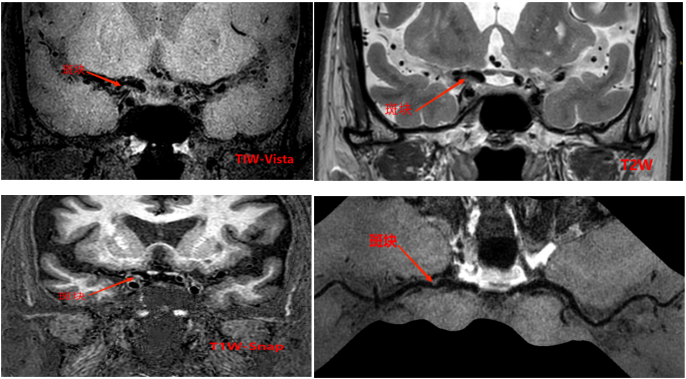

4df07320cb4936fc878ee04289f17171.png

以上4图平扫的T1W-VISTAT2WT1W-3D-SNAP都发现大脑中动脉M1段的大小为1.2*1.5*2.8mm等低信号斑块。

6c7180e7ed935be81a1d0dac685b2bb3.pngf8d20e7e820aa9111b30f3e48b62d51c.png

上图是打药后扫描的T1W-VISTA+C图像,斑块表现为轻度强化,综合考虑为不稳定斑块。这种情况需要慎重处理,斑块破裂和脱落风险比较大,建议经药物治疗后随访复查。